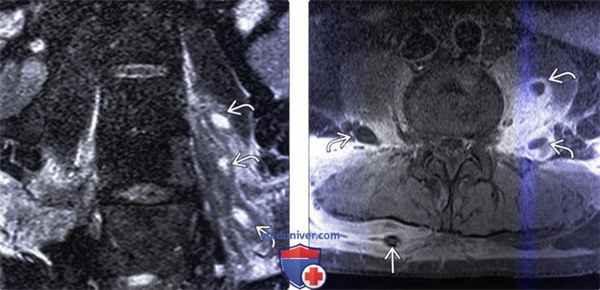

(Слева) Фронтальный срез, STIR МР-И: в толще отечной левой поясничной мышцы видны множественные гиперинтенсивные жид костные скопления. Эти паравертебральные абсцессы скорее всего гематогенного происхождения (пациент являлся внутривенным наркоманом). STIR-режим наиболее информативен в отношении раннего выявления паравертебральных очагов воспаления.

(Справа) Аксиальный срез, Т1-ВИ, FS с КУ: множественные небольшие контрастирующиеся по периферии и гипоинтенсивные в центре жидкостные образования в толще обеих поясничных мышц. Поверхностные абсцессы были дренированы чрескожно со стороны спины.